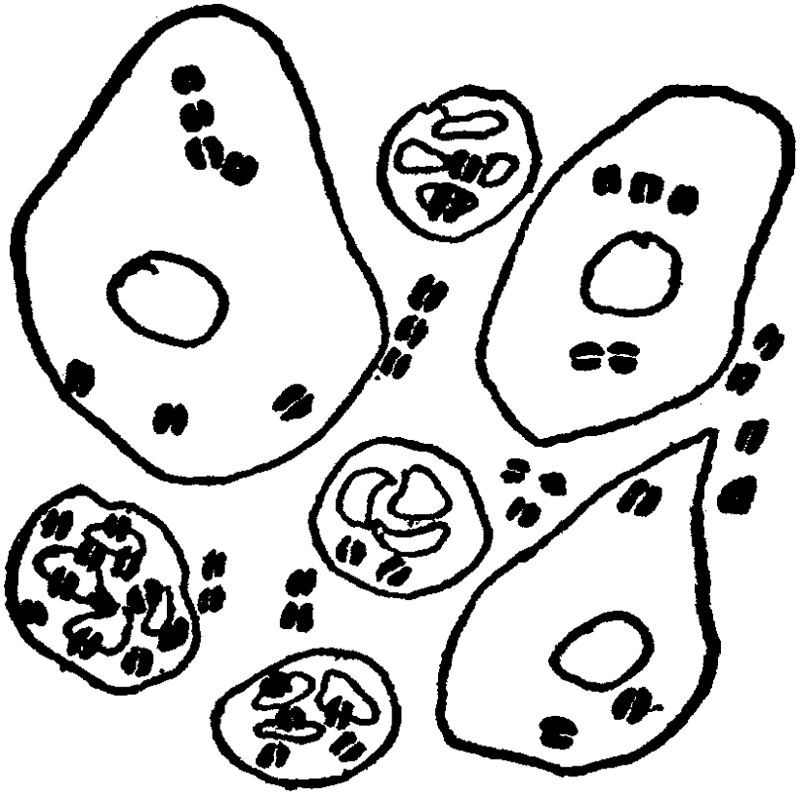

Number of Ova. When the female infant is born, her ovaries contain as many ova or eggs as they ever will contain. In fact, they contain more than they will at puberty. For it is estimated that at birth each ovary contains about 100,000 ova; the majority of these, however, disappear so that at the age of puberty each ovary contains only about 30,000 ova. As only one ovum ripens each month from the time of puberty to the time of the menopause (i.e., about 300 to 400 ova at the utmost during [52]a lifetime), and as only a dozen or two ova would be necessary for the propagation of the race, it seems a superabundance of ova, an unnecessary lavishness. But nature is lavish where the propagation of the species is concerned. A portion of an ovary or of both ovaries might become diseased, and thousands of ova might become unfit for fertilization; nature therefore puts in an extra reserve supply. We see a still more striking example of this extreme extravagant lavishness in man; only one spermatozoön is necessary to impregnate the ovum, and only one spermatozoön can penetrate the ovum; nevertheless each normal ejaculation of semen contains between a quarter and half a million spermatozoa.

The Graafian Follicles. Each primitive or primordial ovum[3] is imbedded in a little vesicle or follicle, which is generally known as Graafian follicle, and there are as many Graafian follicles as there are ova. (The Graafian follicles were first described about 250 years ago—in 1672—by a Delft physician named De Graaf, hence the name.) Until puberty, that is the commencement of menstruation, the Graafian follicles with the oöcytes or primitive [53]ova are in a more or less dormant condition. But with the onset of puberty there commences a period of intense activity in the ovaries. This period of activity is repeated regularly once a month, and it constitutes the process of ovulation and menstruation. The two processes are closely though not causally connected. Ovulation consists in the monthly maturation and extrusion of a ripe ovum; menstruation, which will be further discussed in a separate chapter, consists in the monthly discharge of blood, mixed with mucus from the inside lining of the uterus. Every twenty-eight days, from the [54]time of puberty to the time of the menopause, a Graafian follicle bursts and an ovum is extruded from the ovary. Before the follicle bursts, it swells and enlarges and reaches the surface of the ovary; the whole follicle is congested with blood, but at one point near the surface of the ovary it is pale and thin, and here the rupture takes place.

Corpora Lutea. After the Graafian follicle has burst and the ovum has been pushed out, the cavity that is left does not remain empty and functionless; there is a further process going on there; there is a growth of cells, of a yellowish color, and the follicle becomes filled with a yellowish body, which on account of its color is called the corpus luteum (plural—corpora lutea; luteum in Latin—yellow, corpus—body). This corpus luteum grows in size until it sometimes occupies as much as one-third of the ovary. But there is considerable difference between the corpora lutea of non-pregnant and pregnant women. Up to the end of about a month the corpora lutea are the same, but after that the corpus luteum of the non-pregnant woman begins to get smaller, to shrink, so that at the end of two or three months it is reduced to a small scar and later cannot be noticed at all. The corpus luteum of the pregnant woman keeps on increasing until the end of the second month, remains about the same size [55]until the end of the sixth month, and only then begins gradually to diminish. The corpus luteum of the non-pregnant woman, that is, the one following menstruation, is called false corpus luteum; the corpus luteum following pregnancy is called a true corpus luteum. The corpus luteum acts like a gland and elaborates a secretion which has an influence on the circulation in the uterus and on menstruation. It probably possesses other properties, with which we are not yet quite familiar. The corpora lutea of various animals are now prepared in powder or tablet form and used in medicine in the treatment of certain diseases of women.

Function of the Fallopian Tubes. The function of the Fallopian tubes or oviducts as they are sometimes called is to catch the ovum as it bursts through the ovary and to conduct it from the ovary into the uterus. It is while the ovum is in the narrow lumen of the tube that the spermatozoön which has travelled up from the uterus usually finds it, and it is in the tube, near its entrance to the womb, that impregnation usually takes place. After the ovum [56]is impregnated or fecundated, it slowly moves down to the uterus, where it attaches itself and remains and grows for nine months, until it is ready to come out and start an independent life.